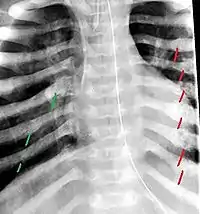

Multiple rib fractures in an infant. Red are old and healed. Green are newer.

Fractured ribs in various stages of healing, typically seen from squeezing injury. Red shows old healed fractures. Green is newer fracture.